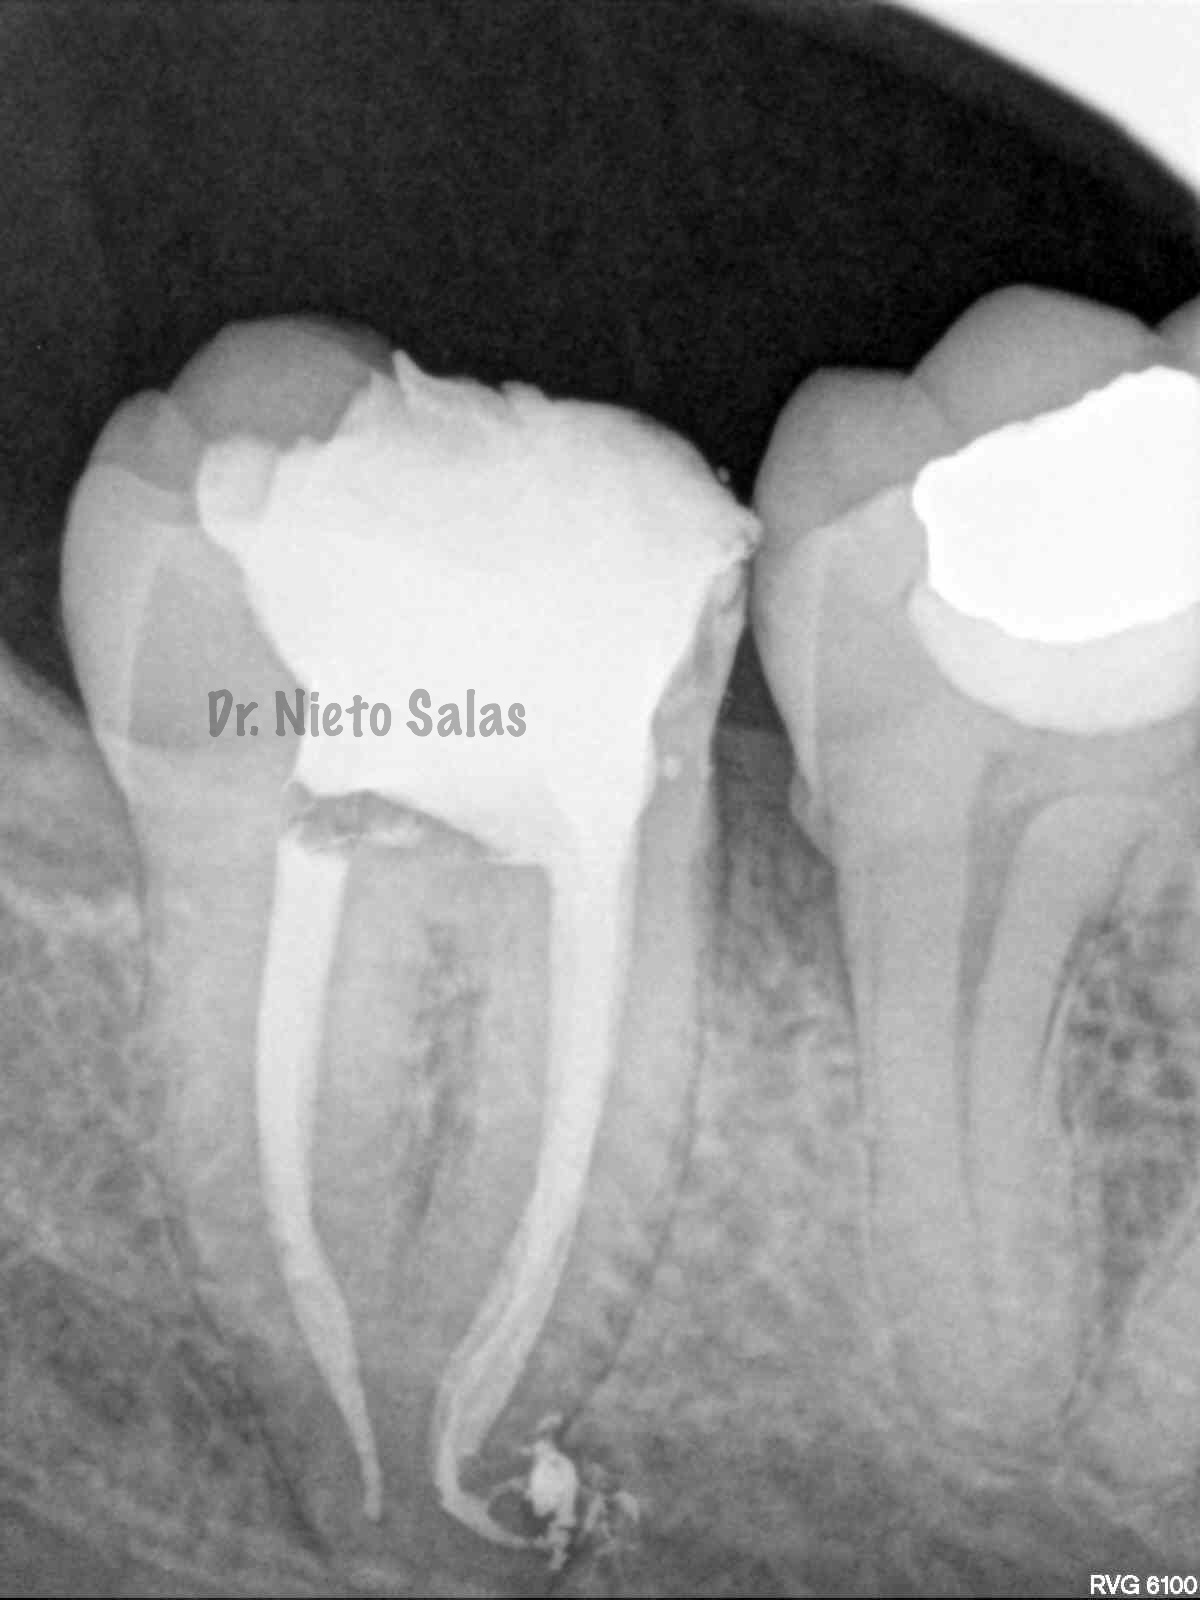

Así pues quedaría el sellado hermético y tridimensional:

Y una en las demás proyecciones MESIO Y DISTO:

2. disculpe, en las imagenes de la entrada de los conductos, era dos conductos distales o era solo uno ?? muchas gracias y enhorabuena por el casa, es perfecto !!

3. Dr Nieto Salas, en la imagen en que se ven la camara con la entrada de los conductos y la gutapercha, el orificio de entrada en distal era muy ancho, a parte de conductos laterales, localizo un conducto o dos conductos ?? ( la duda es por lo ancho de la entrada). El caso es maravilloso. Le doy mi enhorabuena.

4. Hola Juan,

en ese caso en particular, el número de conductos era solamente uno, ya sabes que los conducto distales en muchas ocasiones tienen forma ovalada, con lo que la entrada puede corresponder con las imágenes.